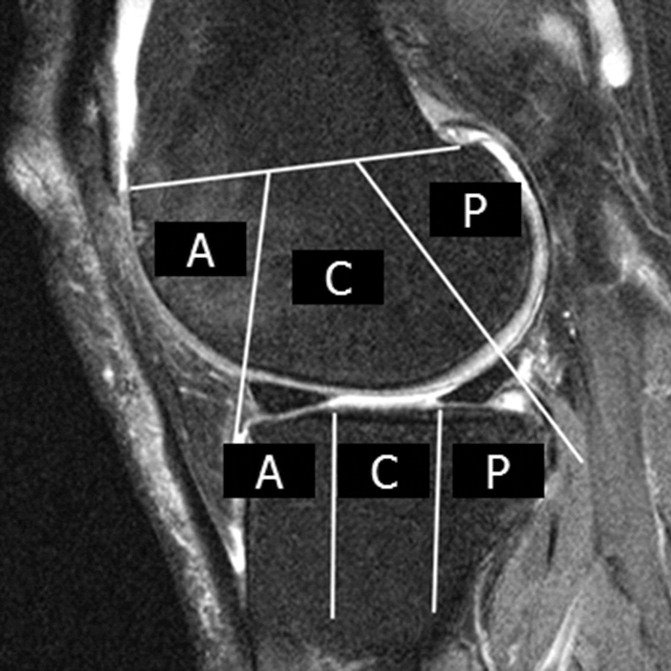

• meniscal status

• meniscal extrusion

Meniscus

Increased risk of replacement:

• Maceration in the medial compartment (OR 1.8)

• At least one subregion in medial compartment with any meniscal damage (OR 1.6)

• Extrusion and lateral compartment damage not correlated